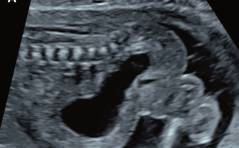

Sonoquiz – Was ist das?

Zuweisung einer 29-jährigen Primigravida in der 17 4/7 Woche mit V.a. fetale Megazystis. PDF Dokument